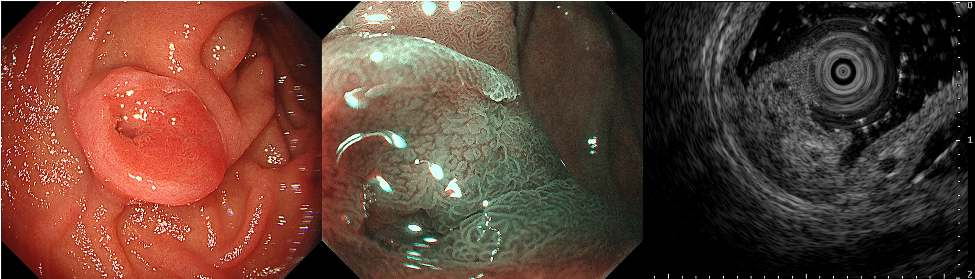

食管胃十二指肠镜:病变呈黏膜下肿瘤(SMT)样形态,表面可见浅红色假性凹陷及中央深凹陷。窄带成像:病变区域呈现类似胃黏膜的环形腺管开口,但未见异常微表面或微血管结构。超声内镜:未见肿瘤侵及黏膜下层(图A)。

图A